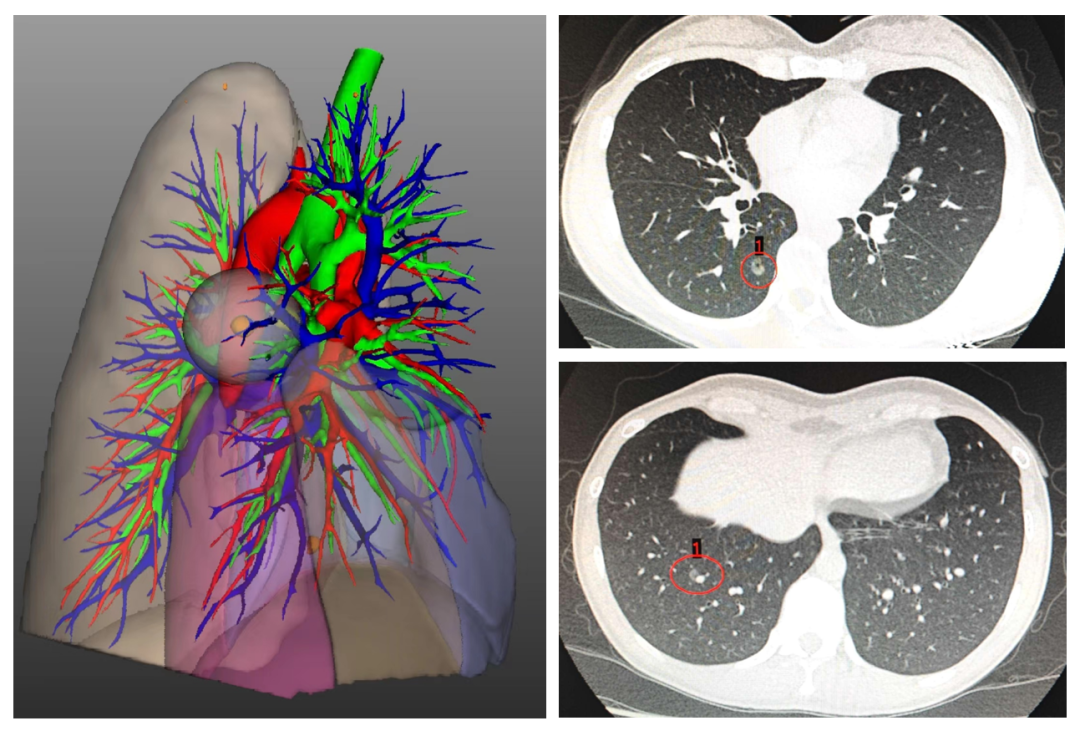

▲ CT及三维重建示右下肺高危结节2枚Juz帝国网站管理系统

经多方打听,王女士找到福建医科大学附属第一医院胸外科赖繁彩主任医师。经过详细的阅片分析,赖繁彩主任医师考虑王女士右下肺的2枚高危结节均是小于2cm的磨玻璃结节,其中一结节位置较深(位于S9+10之间),若行手术切除,需进行复杂的RS6+RS9+10段切除术。Juz帝国网站管理系统